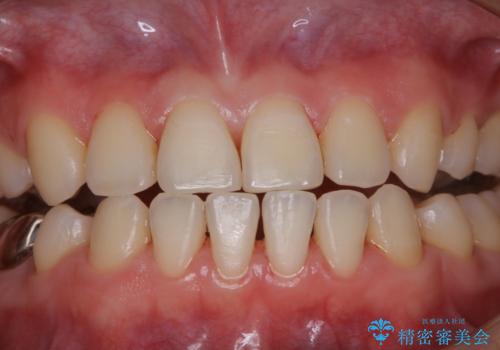

治療の前にPMTCできれいでツルツルな歯に

- 今後治療を進めていく予定で、まずはきれいにクリーニンングから行いたいとのことでした。PMTC60分コースを行いました。